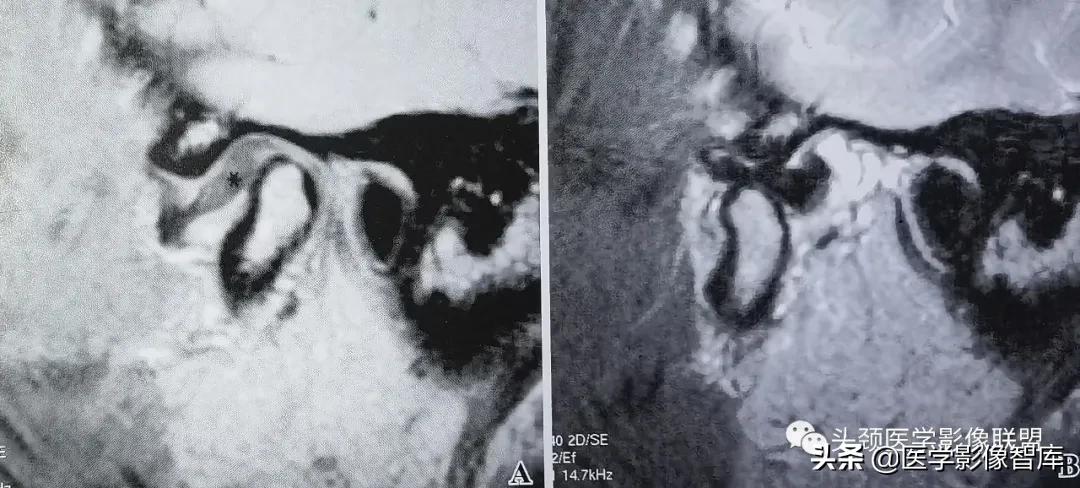

图1 可复性关节盘前移

A. 矢状面闭口PDWI示:关节盘后带(黑星)位于下颌髁突前方;B.矢状面开口T2WI示:盘 一 髁关系恢复正常。关节上腔内有少量积液。

可复性盘前移的临床主要表现为弹响。它是指闭口位时关节盘后带位置位于下颌髁突横嵴顶的前方;张口时,髁突向前移动撞击关节盘后带发生弹响,关节盘向后反跳,随后恢复到正常盘一髁关系。可复性盘前移位的MRI表现特点为:矢状面闭口位上 (图1A) ,低信号的关节盘位于下颌髁突横嵴顶12点位的前方,关节盘双板区与后带之间的界限较为模糊;矢状面张口位上 (图1B) ,盘一髁关系恢复正常。即下颌髁突横嵴顶12点位的上方是关节盘中间带,关节盘后带位于下颌髁突的后方。大多数情况下,可复性盘前移位时的关节盘外形少有形态上的异常改变。不完全性关节盘移位多为可复性盘移位。